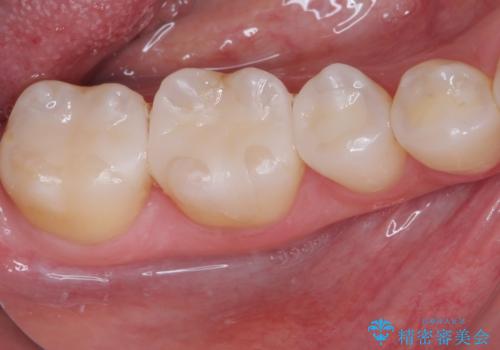

銀歯をセラミックにしたい セラミックインレー修復

- 銀歯をセラミックにしたいとのことで来院された患者様です。

まず麻酔をして銀歯を外し、むし歯を除去し、形を整えて型取りします。

そして次の来院時、セラミックインレーを装着し、噛み合わせなどの調整を行います。

それを左右に分けて行いました。

インレーを装着するときは、唾液や血液による接着力の低下を避けるためにラバーダム防湿を行いました。

自然な色調で大変満足されました。